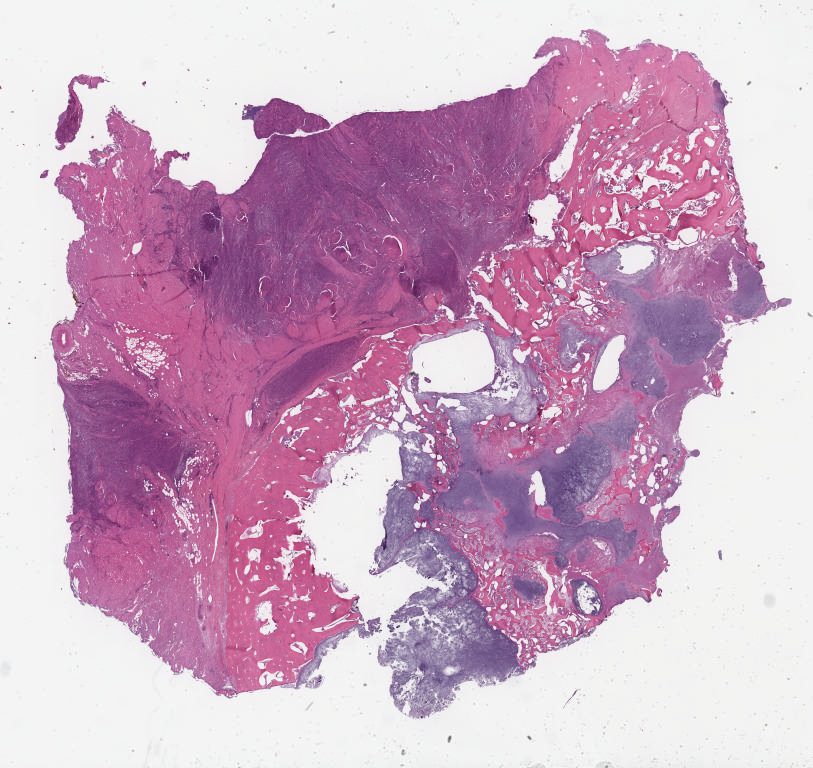

Case1.svs